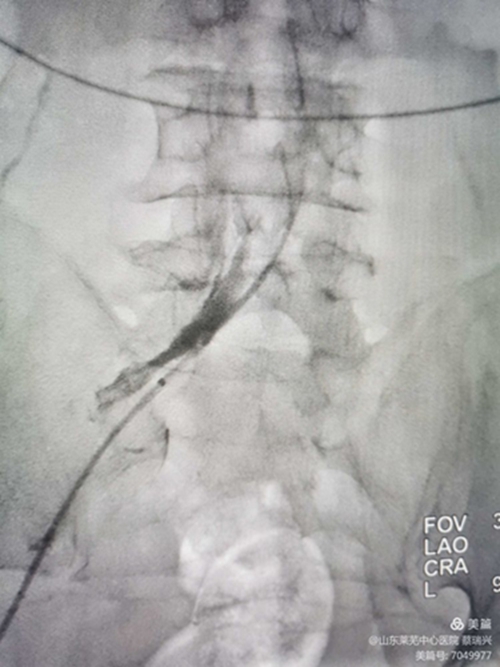

女性,55歲,左下肢腫脹2天入院,疼痛,無明顯功能障礙。左下肢I(xiàn)I度水腫,脹力高。彩超示,左下肢股淺靜脈、股總靜脈、髂外靜脈血流不暢,見有血栓,呈低回聲。髂總靜脈觀察不清。肺動(dòng)脈CTA示無栓塞。取右股靜脈入路,造影證實(shí)左髂總靜脈閉塞,開通后,左下肢深靜脈造影示左下肢股淺靜脈、股總靜脈、髂外靜脈均有充盈缺損,留置溶栓導(dǎo)管6天。今天給予左髂總靜脈支架成形術(shù)。如圖,溶栓導(dǎo)管造影證實(shí),左髂總?cè)杂兄囟泉M窄,血流不暢,易再閉。

與右髂總匯合處,重度狹窄。

取出濾器,預(yù)行左髂總靜脈成形術(shù),但又閉塞,導(dǎo)管不能通過。